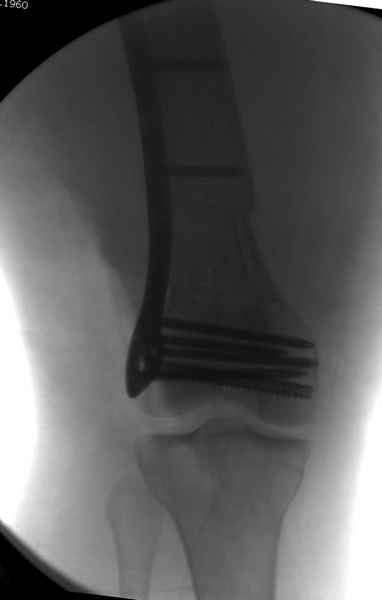

При наличии различных имплантов, любые варианты: слева (полу) открытым - мининвазивным, а справа закрытым интрамедуллярным методом, его считаем более чем приемлемым для фиксации данных переломов.

Проксимальная и дистальная блокировка, независимо от техники введения штифта, ретроградно или антеградно, гарантирует сращение сегментарных переломов бедра без укорочения. Штифты диаметром 12 мм с блокировкой сверху и вниз двумя шурупами выдерживают вес 75 кг больного, что позволяет раннюю профилактику контрактур.

Из-за вариабельности установки дистальных шурупов и возможности перкутанного введения проксимально предпочитаем DePuy Polyax, хотя на сегодняшнем маркете множеств вариантов фиксации дистального бедра перкутанном методом.